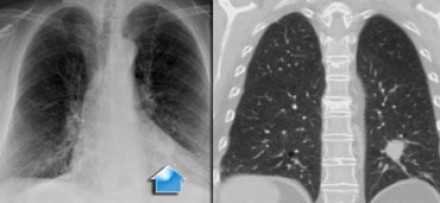

- Т2 - опухоль от 31 до 50 мм в диаметре в наибольшем измерении, или опухоль в сочетании:

- с вовлечением главного бронха, независимо от расстояния до карины, но без её поражения

- с поражением висцеральной плевры

- с ателектазом или обструктивным пневмонитом, который располагается в прикорневых отделах, вовлекает часть легкого или все легкое

- Т2а - опухоль от 31 до 40 мм в диаметре в наибольшем измерении, или размер не может быть определен (например, когда опухоль неотделима от ателектаза)

- Т2b - опухоль от 41 до 50 мм в диаметре в наибольшем измерении

![]()